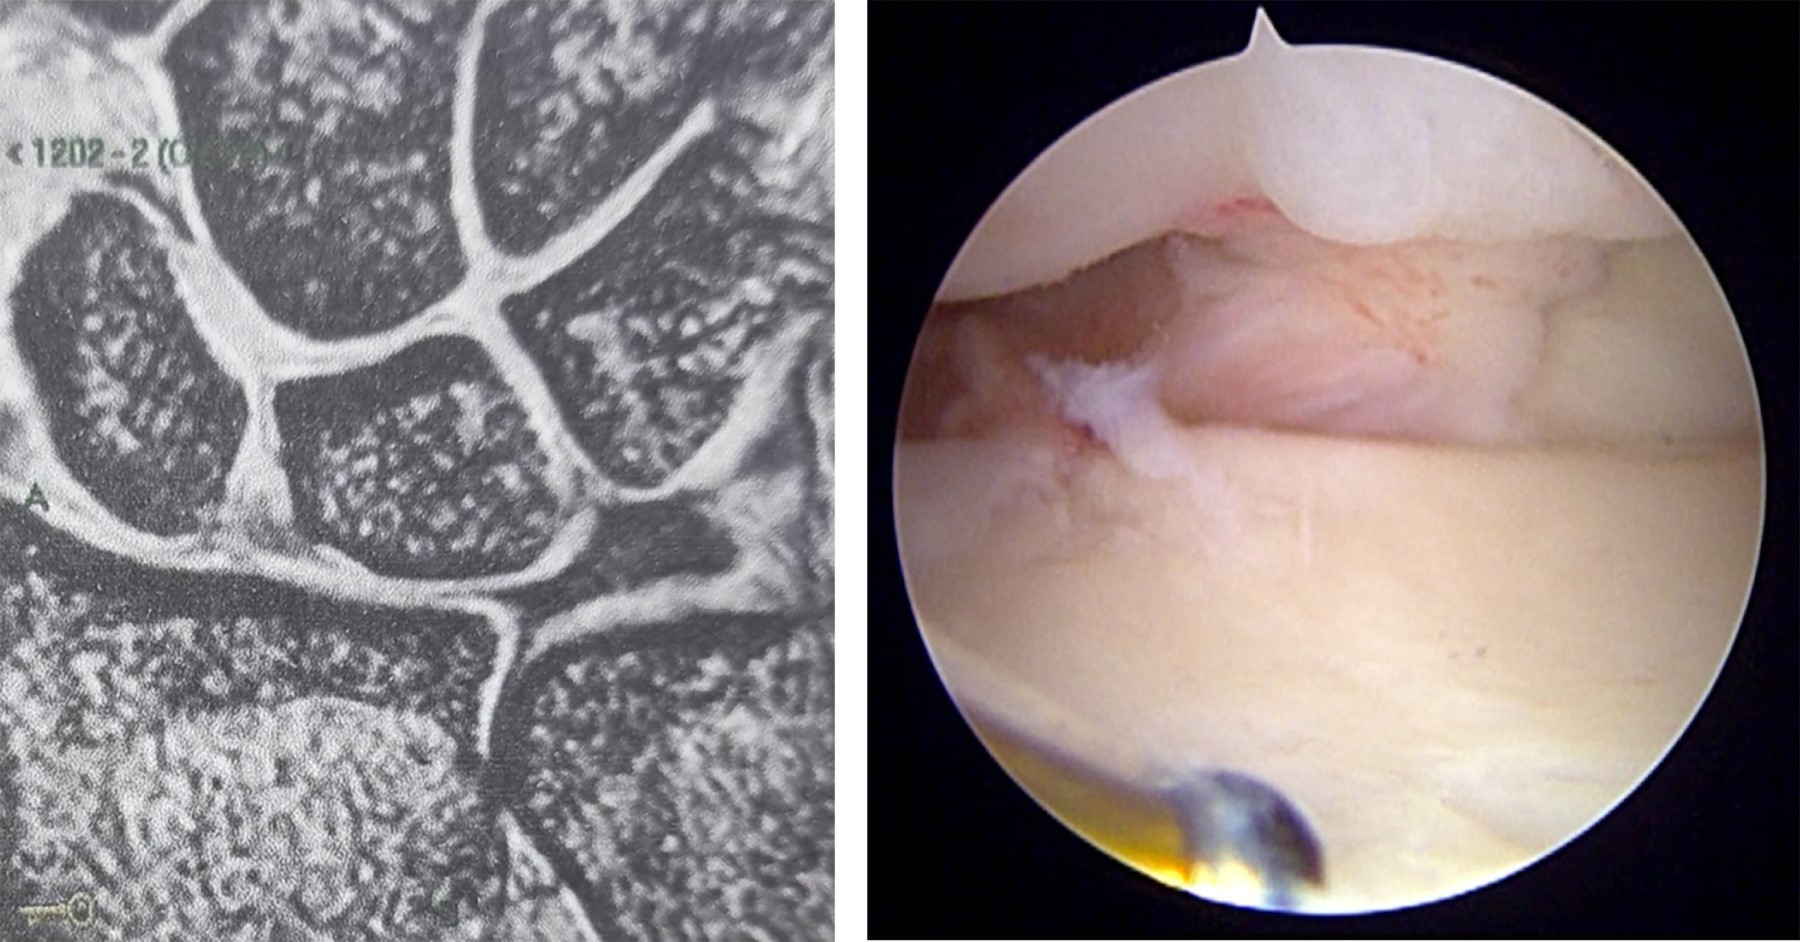

Se incluyeron a todos los pacientes que cumplieron con los criterios de inclusión de los que se tiene registro para este estudio, aunque la muestra fue pequeña. Asimismo, se decidió agotar todas las opciones terapéuticas no invasivas antes de pasar a la reparación quirúrgica mediante artroscopía de muñeca, por lo que existe una mayor ventana de tiempo entre la resonancia magnética y la artroscopía de muñeca, pudiendo dar espacio a una mayor cantidad de lesiones y/o gravedad de estas. En la Figura 2 se observa lesión del ligamento escafosemilunar observada mediante resonancia magnética y artrosocopia de muñeca en el mismo paciente. En la Figura 3 se observa lesión del fibrocartílago triangular Palmer 1D. Y en la Figura 4 se observa lesión del ligamento radioescafogrande.

Figura 2

Figura 4